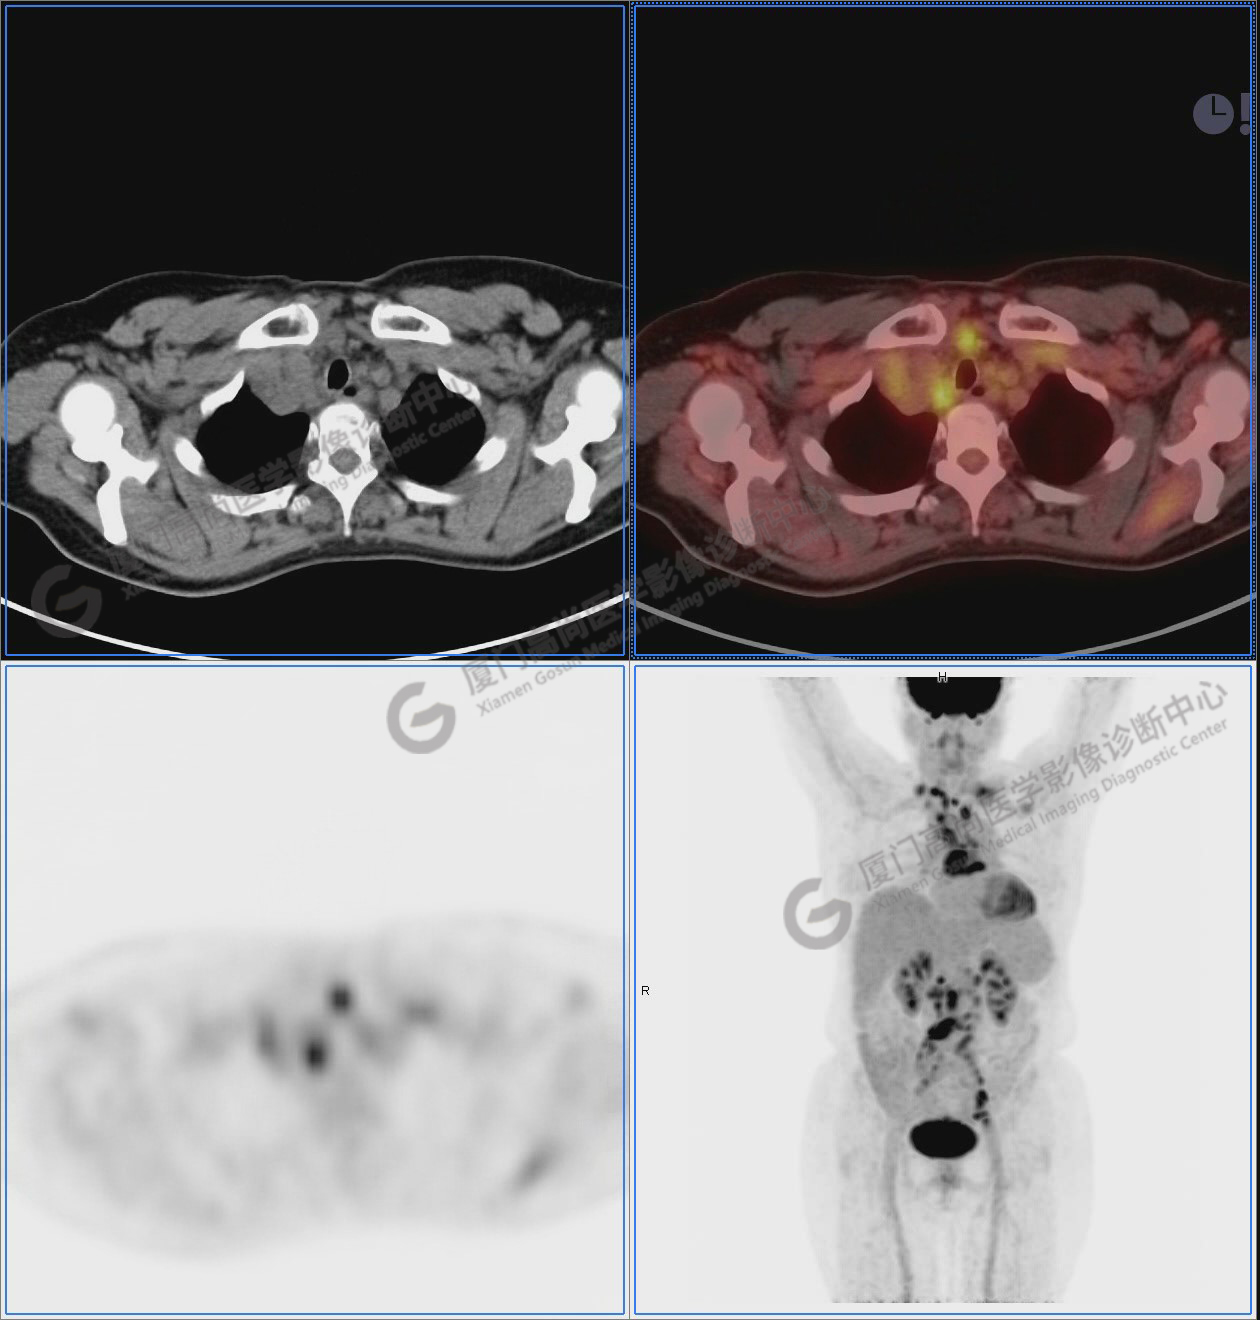

PET/CT影像圖

圖2-9:雙側(cè)鎖骨區(qū)、縱隔、右側(cè)內(nèi)乳區(qū)、腸系膜緣、腹膜后、雙側(cè)髂血管旁及盆腔多發(fā)腫大淋巴結(jié)影,代謝不同程度增高,考慮為轉(zhuǎn)移。

圖10-11:子宮頸軟組織腫塊,代謝異常增高,考慮為宮頸癌。

圖12-13:延遲2小時后,宮頸腫塊糖代謝進一步增高。